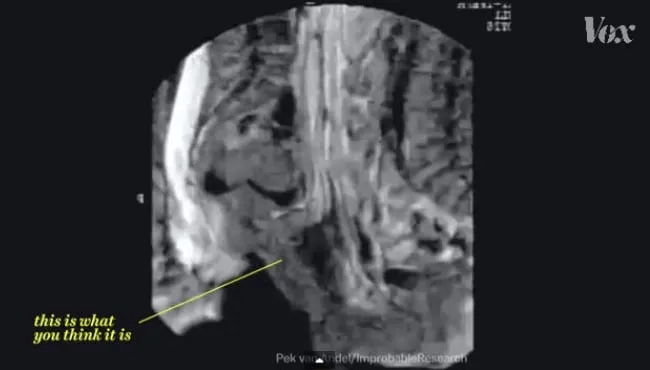

Grâce à l’IRM… (lire la suite)